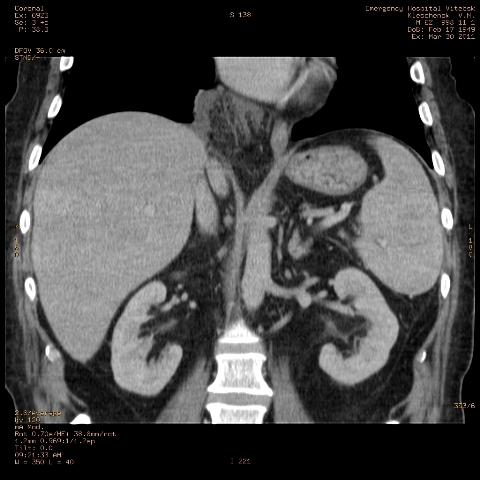

при исследовании органов брюшной полости по поводу абсцесса печени, в нижнем этаже средостения выявлено образование неоднородной плотности (-5-+25), при в/в контрастировании - не контрастируется, при per os - затёков из пищевода нет, неправильно овальной формы. предположительно киста перикарда? спасибо за помощь!

Может быть enteric duplication cyst. Как бы есть грыжа жира hiatal. И что с печенью? Мало срезов.